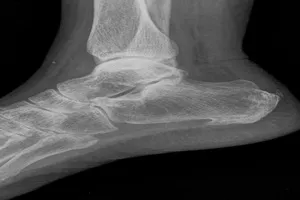

9. 골절

외부의 강한 충격이나 외상으로 인해 뼈가 부러지는 것을 말합니다. 골절 부위는 심한 통증과 부종을 동반하며, 경우에 따라 변형이나 기능 장애가 발생할 수 있습니다. 골절의 정도와 위치에 따라 깁스 고정, 수술 등 다양한 치료 방법이 사용됩니다.